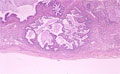

• 5.Lung, Pleura

• (12)Interstitial pneumonia(diffuse alveolar damage (DAD) / acute interstitial pneumonia (AIP))

Macroscopic views: The cut surface is firm and whitish in color.